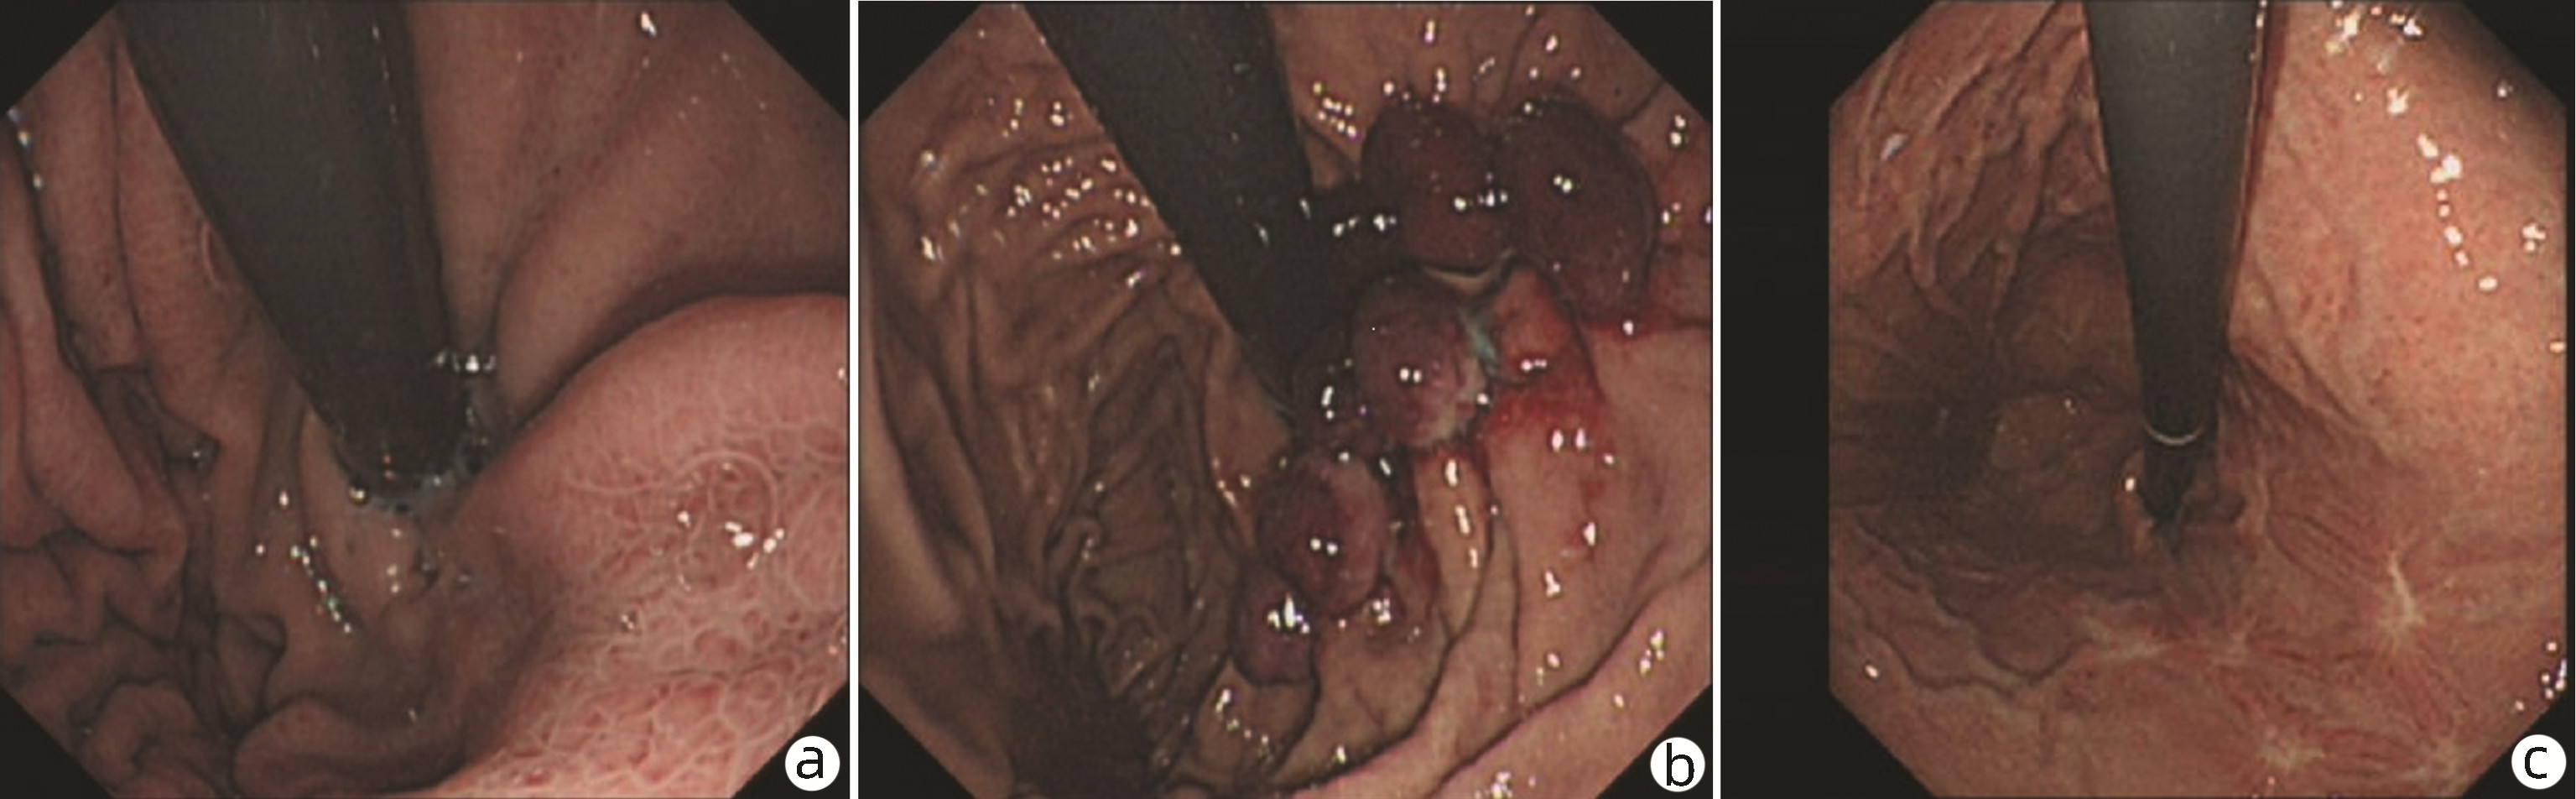

Endoscopic sequential ligation for treatment of esophageal and gastric varices with duodenal varices: A case report

Hao WEN, Zhaohui HE, Tong JIANG, Guoqing SHI

2023, 39(3): 637-639. DOI: 10.3969/j.issn.1001-5256.2023.03.024

Abstract(837) HTML (263) PDF (2676KB)(95)

Abstract: